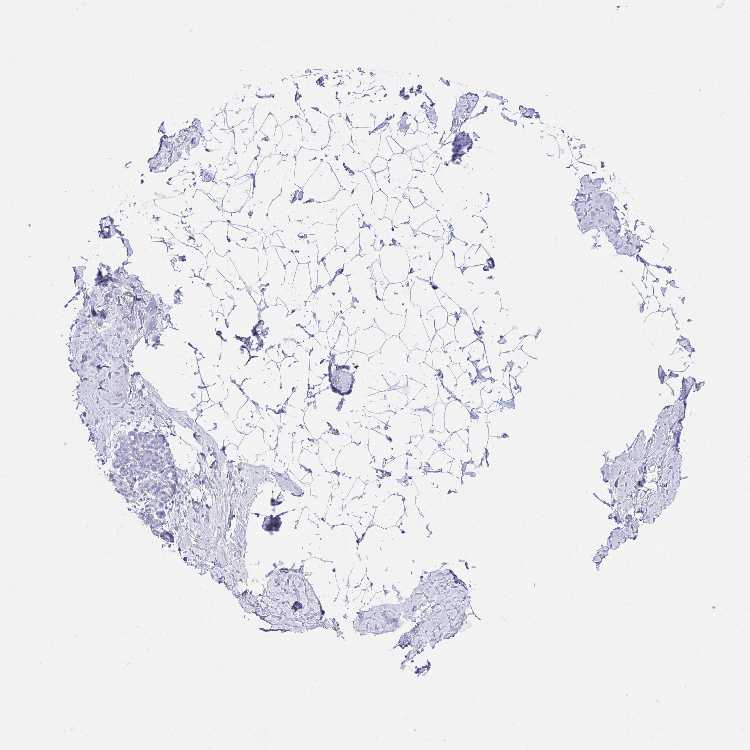

TISSUE PRIMARY DATA BREAST Show tissue menu

BREAST - Antibody stainingi

Antibody staining in the annotated cell types in the current human tissue is reported as not detected, low, medium, or high, based on conventional immunohistochemistry profiling in selected tissues. This score is based on the combination of the staining intensity and fraction of stained cells.

Each image is clickable and will lead to virtual microscopy that enables deeper exploration of all samples and also displays staining intensity scores, fraction scores and subcellular localization as well as patient and tissue information for each sample.

Antibody HPA044848Antibody HPA056897

Adipocytes Not detectedNot detected

Glandular cells Not detectedNot detected

Myoepithelial cells Not detectedNot detected